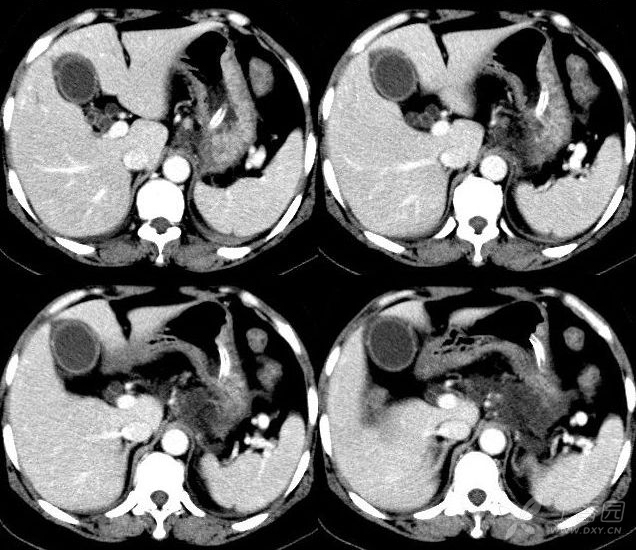

罕见的肝硬化巨大结节影像学如何诊断病例学习

图示结节大于3 mm,属大结节型肝硬化.

病 理 分 类: 小结节性肝硬化 d: 3-5mm 最常见 大结节性肝硬化 d: 1